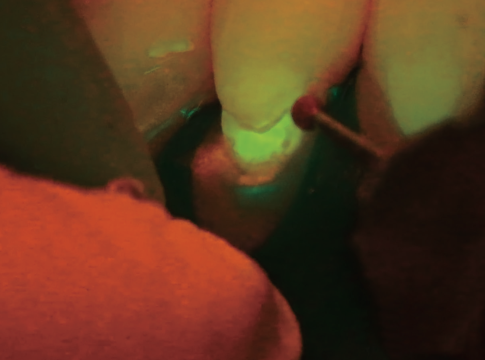

Fluorescence mode(オプション)

世界で初めて蛍光モードを内蔵した歯科用手術顕微鏡EXTARO 300はこれまで以上に有効な診断、効率的なワークフローをサポートします。

手術顕微鏡で拡大した視野下にて歯石・歯垢が付着している箇所は赤色、正常な部位は緑色となるため、カリエスリスクの高い箇所の識別を補助し、処置前後のインフォームドコンセントや治療を効率的に行うことができます。

蛍光モードでの観察

蛍光モードでの処置